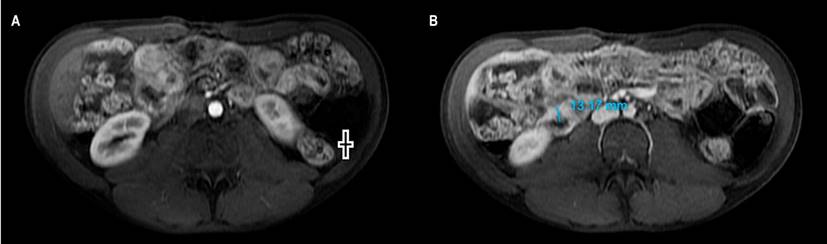

Al mes consultó por dolor abdominal, por lo que se le realizó una nueva tomografía que reportó enteritis en el yeyuno, neumoperitoneo y colecciones. Fue llevado a una laparotomía en la que se evidenció obstrucción de intestino delgado proximal y distal, granulomas en el meso del intestino delgado, perforación del yeyuno medio con plastrón que comprometía el íleon distal y trayecto fistuloso. Se realizó una resección y anastomosis de intestino. Culminado el tratamiento de TB se inició terapia biológica con adalimumab hasta una dosis de mantenimiento de 40 mg subcutáneo cada 2 semanas. La evolución clínica fue favorable, 1 año después asistió a un control ambulatorio de gastroenterología en remisión clínica y sin complicaciones, y una nueva colonoscopia no evidenció alteraciones (Figura 3).

Figura 3 Imágenes de colonoscopia del paciente sin evidencia de actividad de la enfermedad. Imagen propiedad de los autores.